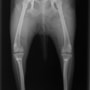

■ 症例20 ポメラニアン 8ヶ月 1.8kg

左右膝蓋骨脱臼 グレードⅢ

2ヶ月前から間欠的跛行が認められ、両膝の膝蓋骨脱臼整復術を行った。